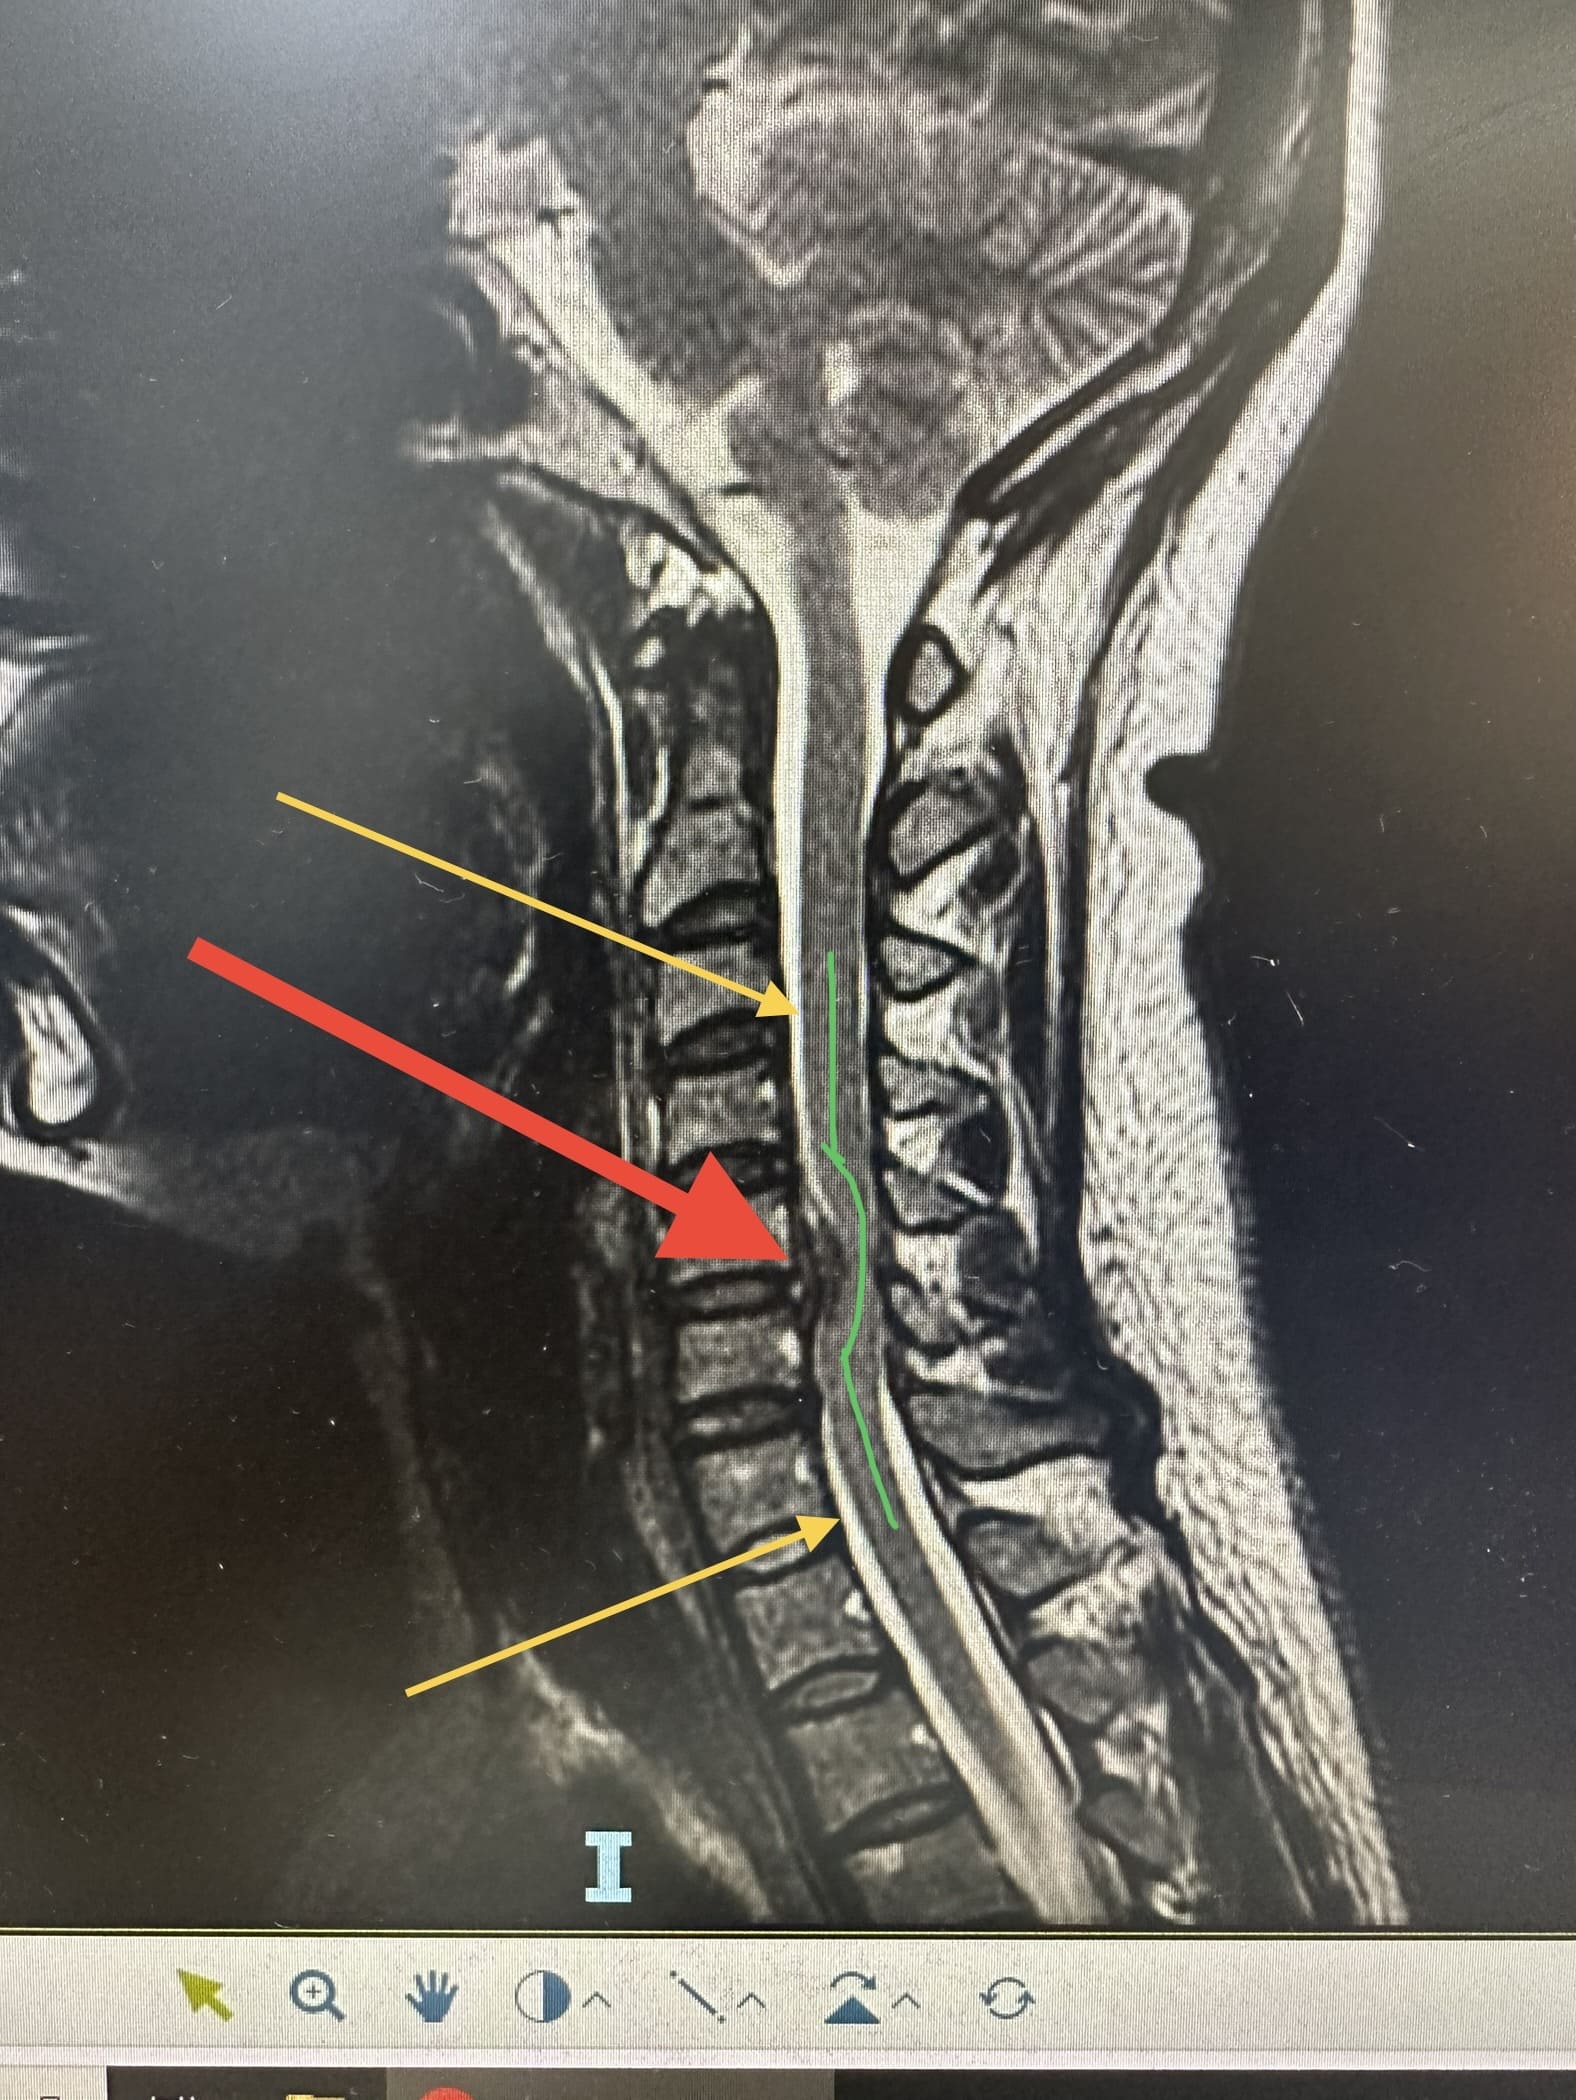

Uma hérnia de disco cervical ocorre quando o material do disco intervertebral se desloca ou se projeta para fora de sua posição normal e comprime as estruturas circundantes, como os nervos ou a medula espinhal.

As duas principais técnicas cirúrgicas para hérnia de disco cervical são:

A artrodese cervical é um procedimento cirúrgico que envolve a fusão de duas ou mais vértebras da coluna cervical. A fusão é realizada usando parafusos, pinos ou placas.

Exames como ressonância magnética (RM), tomografia computadorizada (TC) e radiografias são frequentemente realizados para diagnosticar a condição da coluna cervical antes de decidir pela cirurgia.